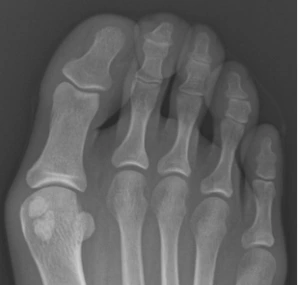

종자골 이분증 (이분종자골)

- 엄지발가락 아래에 위치한 종자골이 선천적으로 두 개로 나뉜 상태를 의미합니다.

성장 과정에서 뼈가 완전히 합쳐지지 않아 X-ray에서 반으로 나뉜 것처럼 보이는 현상으로

전체 인구의 약 10%에서 발생하며, 양쪽 발에 모두 나타나는 경우는 25%입니다

선척적인 거 외에 심한 충격이 발생하면 후천적으로 발생할 수도 있다는데 나는 뭘까....?

작년 베이징여행을 하면서 하루 2만보씩 4일을

걸은 적이 있는데 그때 엄지발가락 쪽 극심한 통증을

겪고 병원을 갔던 적이 있었는데 그때 병원에서는

무지외반증이라고 이야기를 했었다.

하지만 원인은 이 종자골 이분증이었음을.....